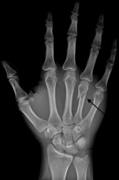

Hand and finger fractures

- XR hand and/or finger(s)

- Consider need for more proximal or distal plain films